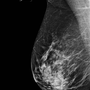

Mamografia digitalizada

A Bio Imagem oferece um dos recentes avanços da mamografia, a Mamografia Digitalizada.

Se assemelha a convencional por usar raios X na produção das imagens porém o sistema é equipado com um receptor digital, o qual converte a imagem numa foto digital e pode ser revisado no monitor do computador, podendo ser alterados orientação, brilho e contraste, visando perceber diferentes áreas da mama.